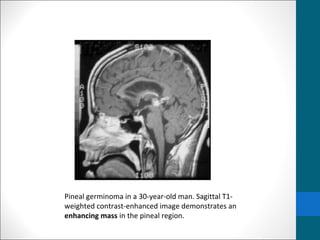

Pineal germinoma in a 30-year-old man. Sagittal T1-

weighted contrast-enhanced image demonstrates an

enhancing mass in the pineal region.

Pineal germinoma ina 30-year-old man. Sagittal T1- weighted contrast-enhanced image demonstrates an enhancing mass in the pineal region.